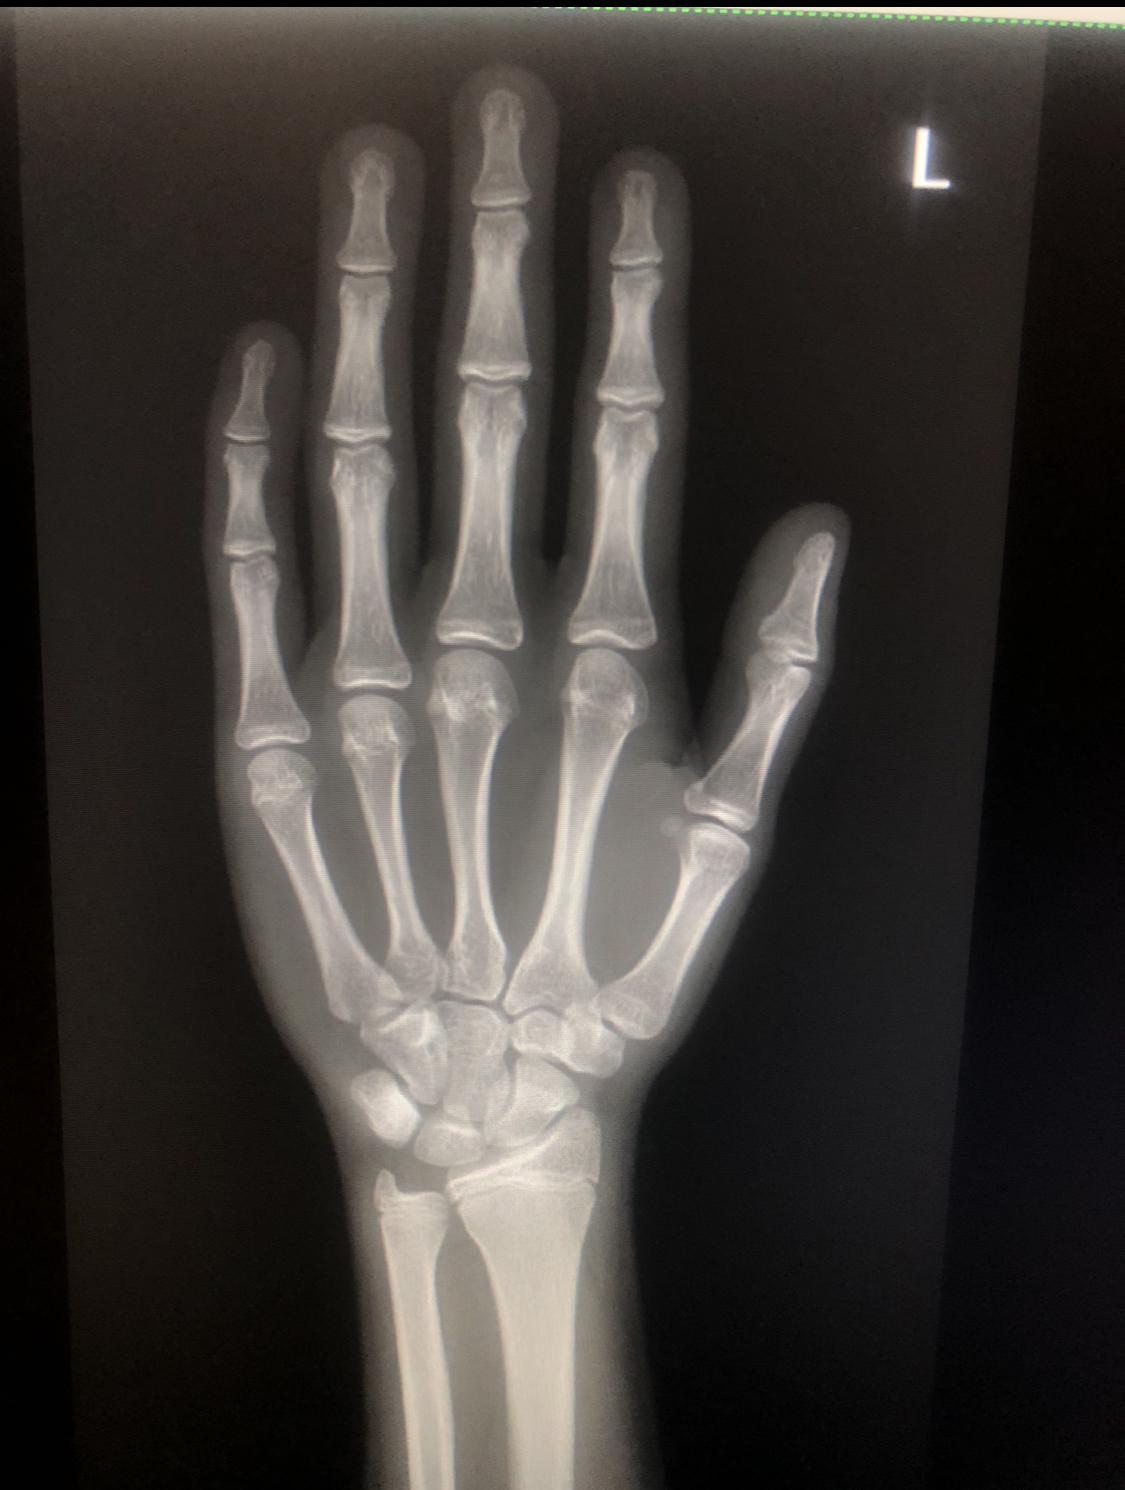

I got an xray of my growth plates today and they were fused at 15 total suacife fuel

:feelsrope::feelsrope: and the doctor told me to get ur knees and pelvic to help me cope with it 168cm ans ugly as fuck never gotten this much ropefuel and i had js gotten like 2mkmth o

IMG 2143